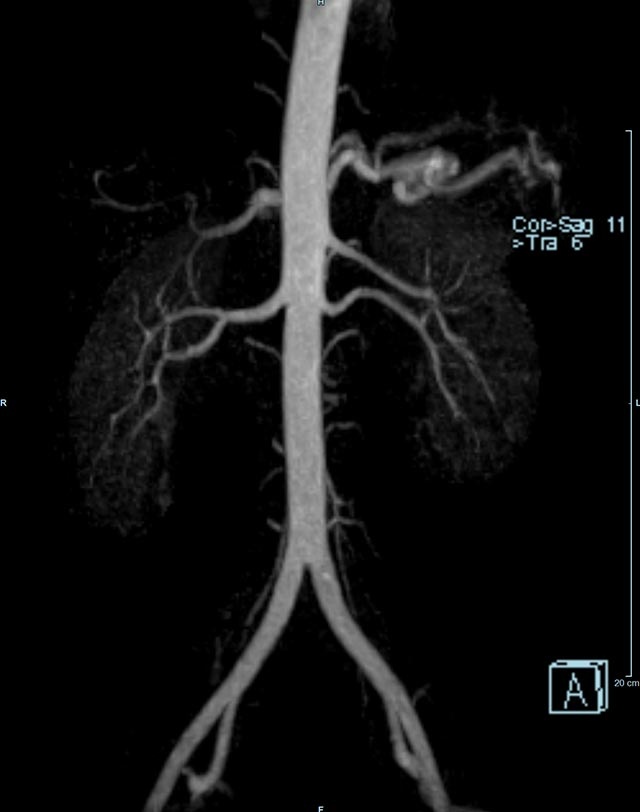

- Bauchgefäße

- Erfassung und Verlaufskontrolle bei arteriellen Aneurysmen (Aussackungen der Arterien), vor allem der Bauchaorta

- Darstellung von Gefäßengen an Nierenarterien, Baucharterien und Becken-/Beinarterien

- MR-Angiographie mit Kontrastmittel

- Erfassung arterieller und venöser Gefäße/Bypässe aller Körperregionen mit 3D-Rekonstruktion

- je nach klinischer Fragestellung zeitaufgelöste MR-Angiographie (4D-MRA) z.B. bei Frage arteriovenöse Fistel/ Shunt oder Darstellung Unterschenkelarterien vor geplanter Bypassoperation.